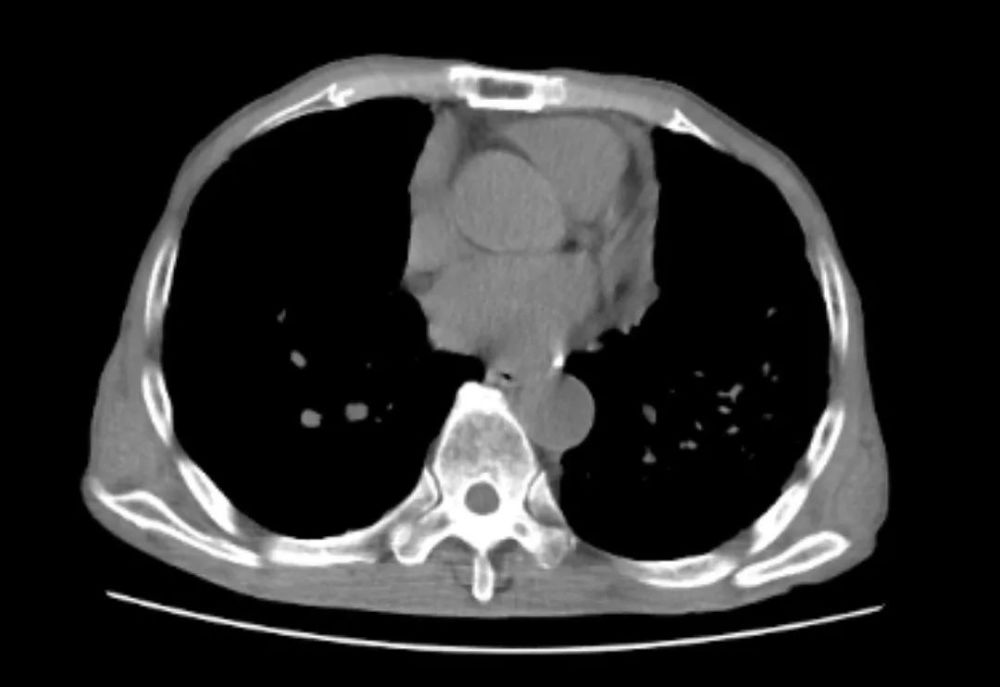

经过入院胸部CT检查 , 可见陈大爷肺内多发由于粉尘沉积引起的肺部肿块 , 融合成团 , 如同白色水泥团块一样 , 紧紧地附着在患者两处肺门的地方 , 初步诊断矽肺 。

陈大爷的CT报告